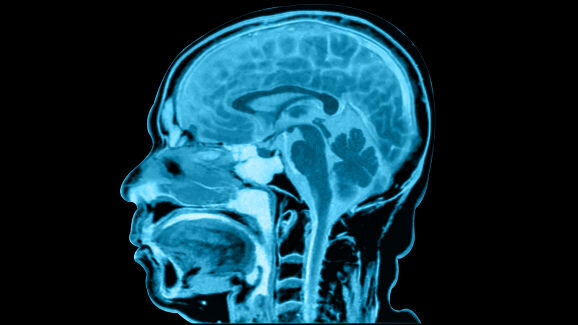

According to Burgess, a form of anterograde amnesia would have been the most obvious explanation for the man’s condition. In this case, the hippocampi, the brain regions responsible for the consolidation of information from short-term memory to long-term memory, are damaged so that memories can no longer be formed and stored correctly. Yet, the man’s brain scans showed no abnormalities. Thus, another possible explanation would have been a psychogenic illness. Burgess conducted detailed psychiatric assessments in order to determine whether the man had suffered any trauma. However, Burgess found that his patient was emotionally healthy and his wife confirmed that there had not been any traumatic events in the man’s life prior to his dentist visit in 2005.